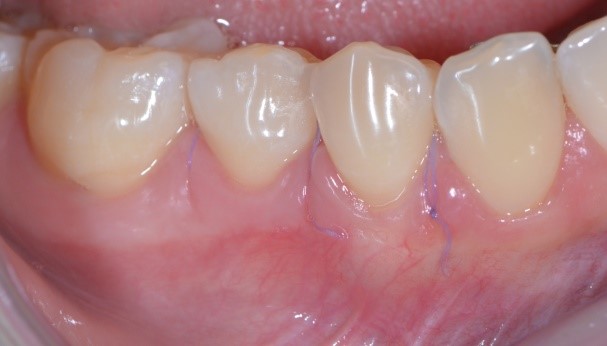

Vediamo il caso iniziale. Francesca presentava recessioni multiple con accentuata ipersensibilità dentinale.

gestione dei tessuti molli - aspetto dei tessuti molli 03